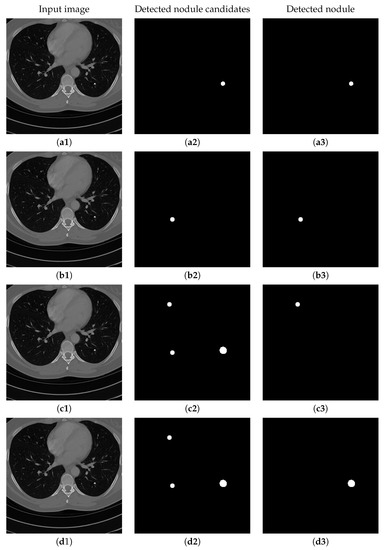

Figure 15 shows the results of detecting pulmonary nodules of using different network modules and different loss functions, including: (1) MSE loss only, (2) MSE-perceptual loss, and (3) MSE-perceptual-dice loss. Using only MSE as loss function results in failure detection of nodules with small sizes and irregular shapes. Without dice loss, the MSE-perceptual loss cannot differentiate the nodule candidates with quite small sizes because the number of pixels belonging to nodule candidates are much smaller than those belonging to background region. In contrast, combining the MSE, perceptual and dice loss can find both large and small nodule candidates, and achieve a good balance in taking the sizes and shapes of the candidates into the account of identification. Furthermore, training the three sub-networks as a uniform framework can enhance the inherent relation and co-operation of these three sub-networks in nodule detection and classification. The accuracy, sensitivity and specificity results shown in Table 7 confirm the above observation.

Figure 15. The results of detecting pulmonary nodule through the proposed network with different loss strategies. Columns from left to right are: input images, detected nodule candidates, detected nodules. Rows from top to bottom are: ground truth detection results, nodule candidates and nodule detection by the proposed network with MSE loss, MSE-perceptual loss and the MSE-perceptual-dice loss.